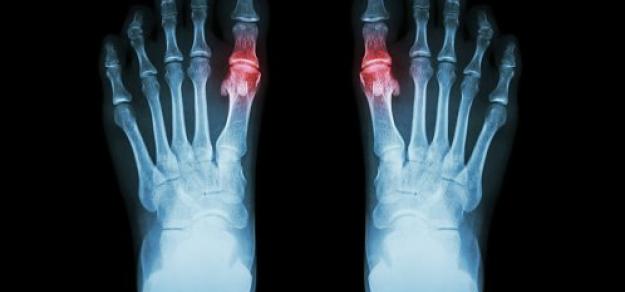

Uso de alopurinol y riesgo de síndrome coronario agudo en pacientes con gota:  estudio de cohorte poblacional

05 marzo 2025

En pacientes con gota y sin enfermedad coronaria, el uso prolongado de alopurinol protege contra el primer síndrome coronario agudo (SCA) en comparación con los no usuarios. Por el contrario, los iniciadores del alopurinol, que posiblemente tenían más inflamación sistémica, tenían un mayor riesgo de SCA por primera vez en comparación con los usuarios a largo plazo. BMJ Open, 27 de febrero de 2025

Seguridad de la profilaxis con colchicina o con antiinflamatorios no esteroides al iniciar el tratamiento reductor de uratos para la gota

23 octubre 2023

En este estudio observacional se comparó el inicio de alopurinol para la gota acompañado de profilaxis con colchicina o con AINE versus alopurinol sin profilaxis asociada. Los eventos adversos fueron más comunes cuando se inició alopurinol con profilaxis, particularmente la aparición de diarrea con el uso de colchicina. Otros eventos fueron poco comunes, lo que brinda tranquilidad a los pacientes y a los médicos para permitir la toma de decisiones compartida. Annals of the Rheumatic Diseases, octubre de 2023.